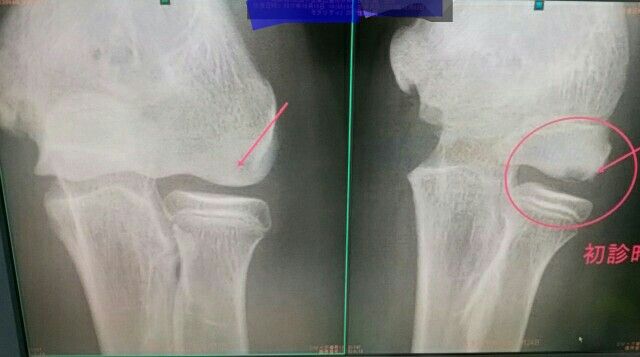

中学生 野球 アスリート

難治性の野球肘

5ヶ月のノースローでしたが

離断した軟骨が完治しました。

1年半後、来院時のレントゲン